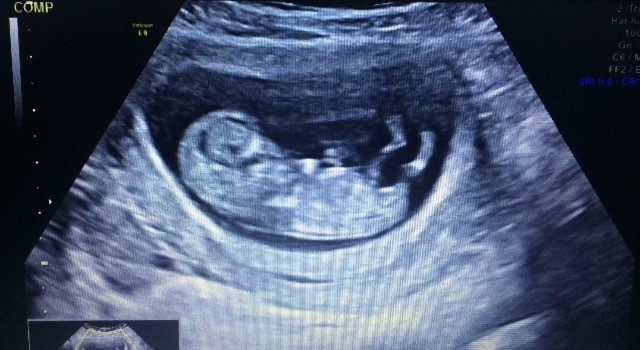

Er i uge 11 på scanningen. Og ved der sidder mange eksperter herinde aner ikke hvad man skal kigge efter  tør i give et bud?? På et af billeder bagfra kan man tydeligt se en tap. Men hun sagde det både kunne være tissemand og klit

Relativt flad pande og burgerlinjer i ryggen på billede 3, umiddelbart en pige